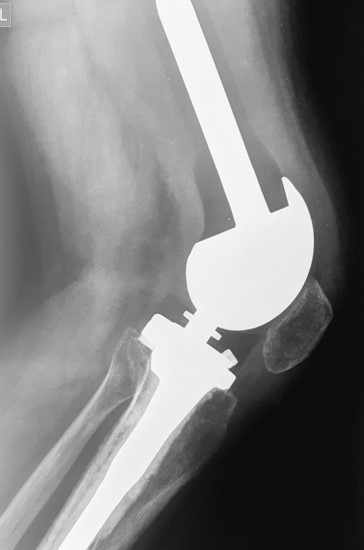

Վիրահատությունից հետո

2. Բժշկական տարբեր կենտրոններում հետազոտվելուց հետո՝ 17-ամյա պատանին դիմել է «Նաիրի» ԲԿ։ Համապատասխան հետազոտություններ անցնելուց հետո՝ բուժառուի մոտ հայտնաբերվել է ոլոքի օստեոսարկոմա (ոսկրային քաղցկեղ): Նախավիրահատական բուժում ՝ քիմիոթերապիա, ստանալուց հետո՝ «Նաիրի» ԲԿ ում կատարվել է օրգանապահպան վիրահատություն : Հեռացվել են ծնկահոդն ու ոլոքի վերին երորդականը: Առաջացած դեֆորմացիան շտկել է Եվրոպայից պատվիրված էդոպրոթեզով, որը հնարավորություն է տվել պահպանել վերջույթի գործառույթը՝ քայլել, վազել և այլն։ Հետվիրահատական շրջանում բուժառուն ստացել է քիմիոթերապիա։ Այժմ գտնվում է բժիշկների հսկողության ներքո։